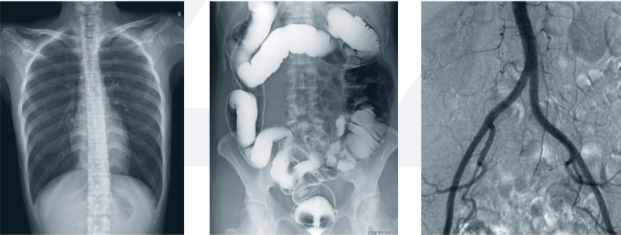

数字平板胃肠机属于多功能X线机,除具有传统胃肠机所有功能外,还有DR平板探测器X线摄影所有功能,主要用于消化道对比造影、消化道吞咽造影、全脊柱拼接摄影、全下肢拼接摄影、ERCP、泌尿系造影、“T”管造影、钡剂灌肠、四肢造影、子宫输卵管造影等各类检查,是检查消化道溃疡、肿瘤、异物等疾病的主要方法之一。

数字平板胃肠机不仅可以做普通的胃、食管钡餐透视,胸腹部的常规透视检查,而且图像更清晰,多了数字化处理过程,还可以实时点片,更便捷的获得实时图像,及时抓拍住病灶图像,为患者留存影像资料。这就像我们的手机抓拍瞬间图像保存到手机相册一样,能够诊断早期食道癌、胃癌、小溃疡等疾病。